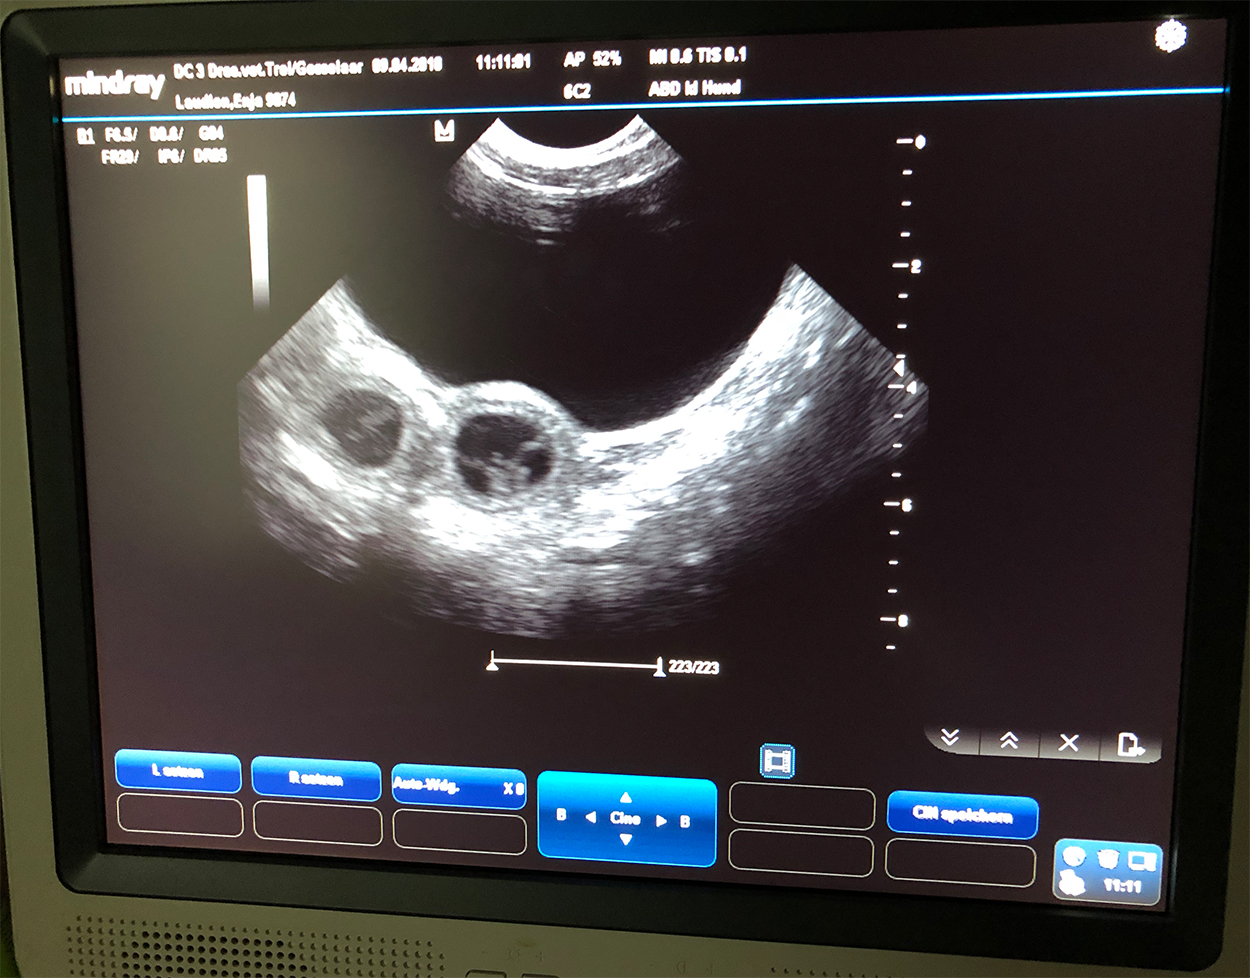

Heute war also der Tag der Tage. Der Tag an dem man Gewissheit bekommt, ob die Hündin aufgenommen hat oder nicht.

Auch wenn Enjas Verhalten zu 100% für eine Trächtigkeit spricht, so wollten wir es gerne

von unserer Tierärztin Heike Trei absegnen lassen. :-)

|

Beim Ultraschall wurden auf Anhieb einige Fruchtanlagen gesichtet. Die genaue Anzahl wollte ich aber nicht wissen.... ein bisschen Spannung soll uns und den Welpeninteressenten schon noch in den kommenden Wochen erhalten bleiben. ;-) |

Wir freuen uns einfach riesig darüber, dass bald kleine G-Bagaluten den Bagalutenhof besetzen werden.

Bis dato werden wir Enja weiterhin fit halten und auf unser Essen aufpassen. :-)